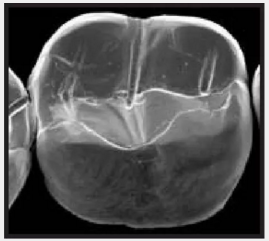

復(fù)合樹脂在即刻充填后,觀察其在電子顯微鏡下的掃描圖像,本次研究選擇了9種具有代表性的復(fù)合樹脂材料。

3.png

Esthet.X HD Dentsply 登士柏